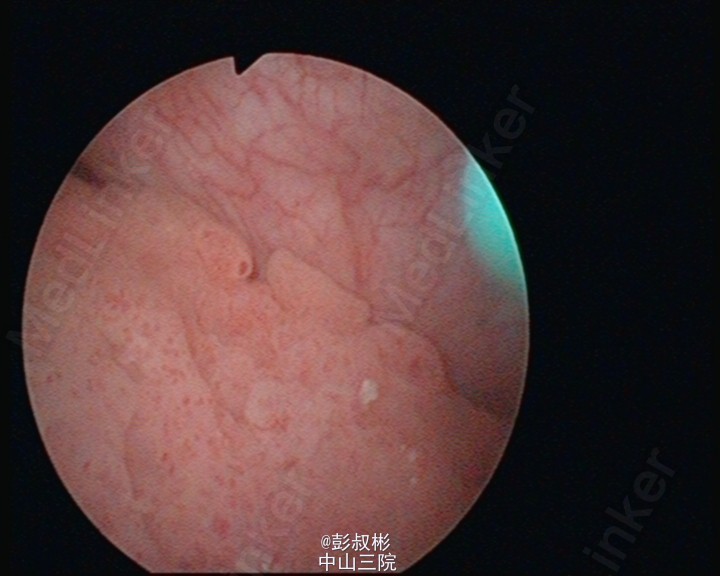

看看那些水草,水。。草。。样子